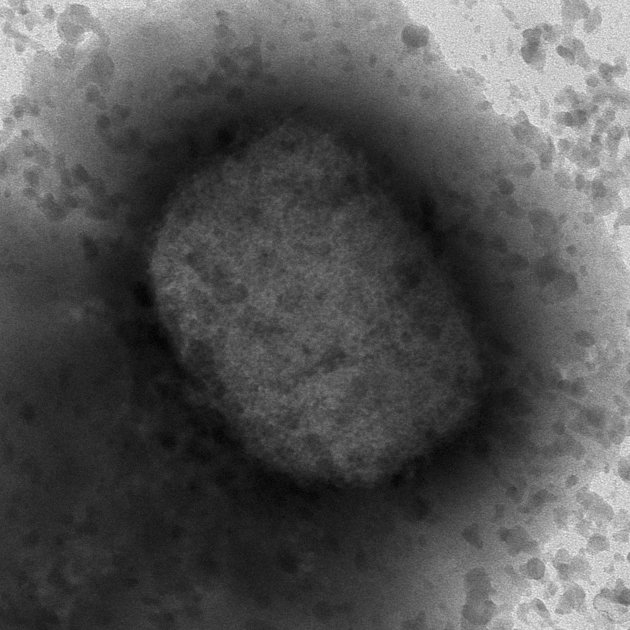

Secuencia completa del virus

Este jueves se ha anunciado que investigadores del Instituto de Salud Carlos III han conseguido el primer borrador de la secuencia completa del virus causante de la viruela del mono que circula por España a partir de las muestras de 23 pacientes. La secuenciación completa ha confirmado que el virus de la viruela de los monos del brote que se está produciendo en España pertenece a un grupo fitogenético de África Occidental, que es la de menor virulencia entre los conocidos y lo que se ha identificado de momento en la mayoría de los países fuera de África implicados en este brote. Según ha informado hoy el Instituto de Salud a Carlos III, se trata de una de las secuencias más completas que se han obtenido hasta el momento, y ha permitido además obtener una cobertura del 100% de los 190.000 pares de bases del genoma de este virus. La secuenciación llevada a cabo a través del Laboratorio de Arbovirus del ISCIII, en colaboración con las unidades de Genómica y Bioinformática, ha contado con las referencias publicadas en los últimos días por otros países (Bélgica, Alemania, Portugal y los EE. UU.), y se ha basado en una tecnología genómica de nueva generación. Los resultados de los análisis señalan que las muestras secuenciadas parecen pertenecer al mismo brote detectado en otros países europeos, ya que los genomas obtenidos apenas difieren de los ya secuenciados en otros países; en concreto, el análisis realizado en el ISCIII concluye que hay muy pocas diferencias con respecto a la secuenciación llevada a cabo en Alemania.